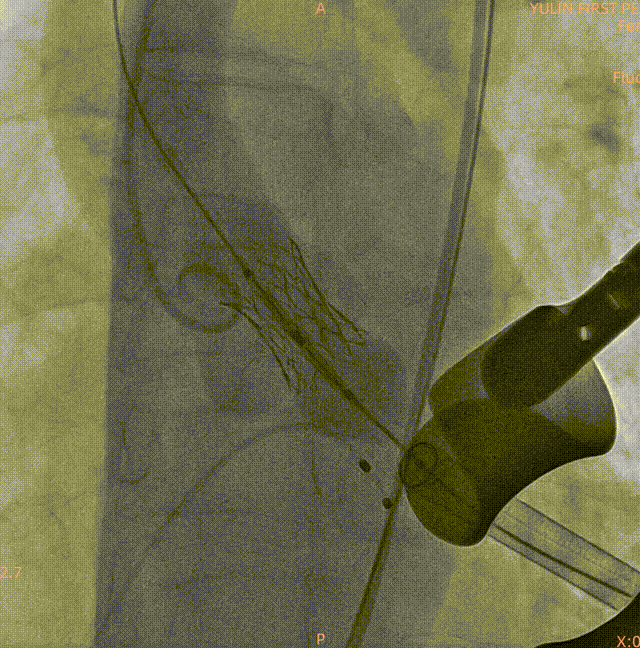

术中影像

主动脉根部造影

19mm球囊预扩

瓣膜定位

23#Renatus瓣膜释放中再次造影定位